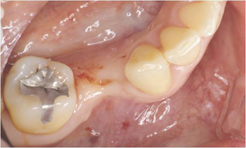

審美インプラント治療(こだわりのインプラント治療)右下小臼歯部

右下小臼歯部

虫歯が進行していたために抜歯となりました

両隣りの歯を削らずにインプラント治療を行いました。